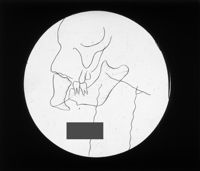

Image[Plaque diapositive. Tissus bucco-dentaires.]